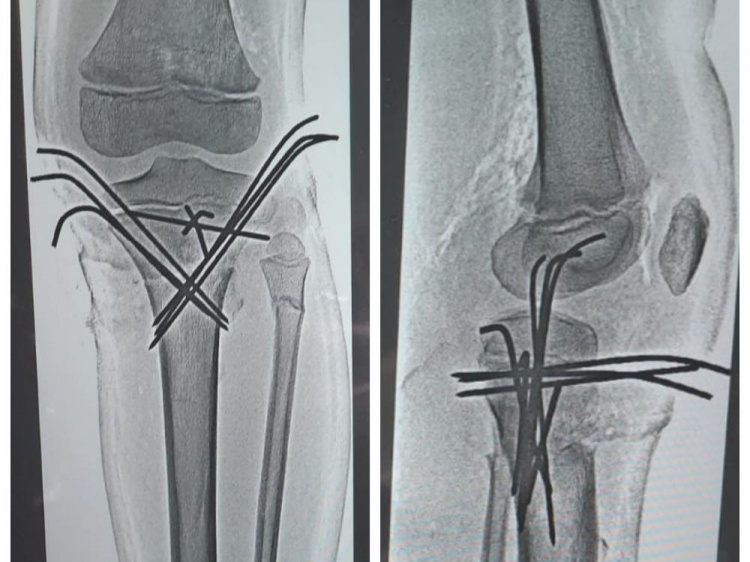

Как сообщили Волжский.ру в комитете здравоохранения , 14-летний школьник попал в серьёзную аварию, столкнувшись с маршруткой. С места аварии его доставили в клиническую больницу скорой помощи №7 в крайне тяжелом состоянии. Врачи диагностировали сочетанную автодорожную травму и травматический шок 2 степени. У юного мотоциклиста насчитали 23 перелома, в том числе закрытую черепно-мозговую травму, перелом ключицы, костей таза со смещением, перелом позвоночника, ушиб легких. Ребенок перенёс уже 4 операции , и до сих пор остаётся в больнице. Ему предстоит ещё несколько хирургических вмешательств по удалению скрепляющих металлических конструкций в конечностях. А после - длительный курс реабилитации.